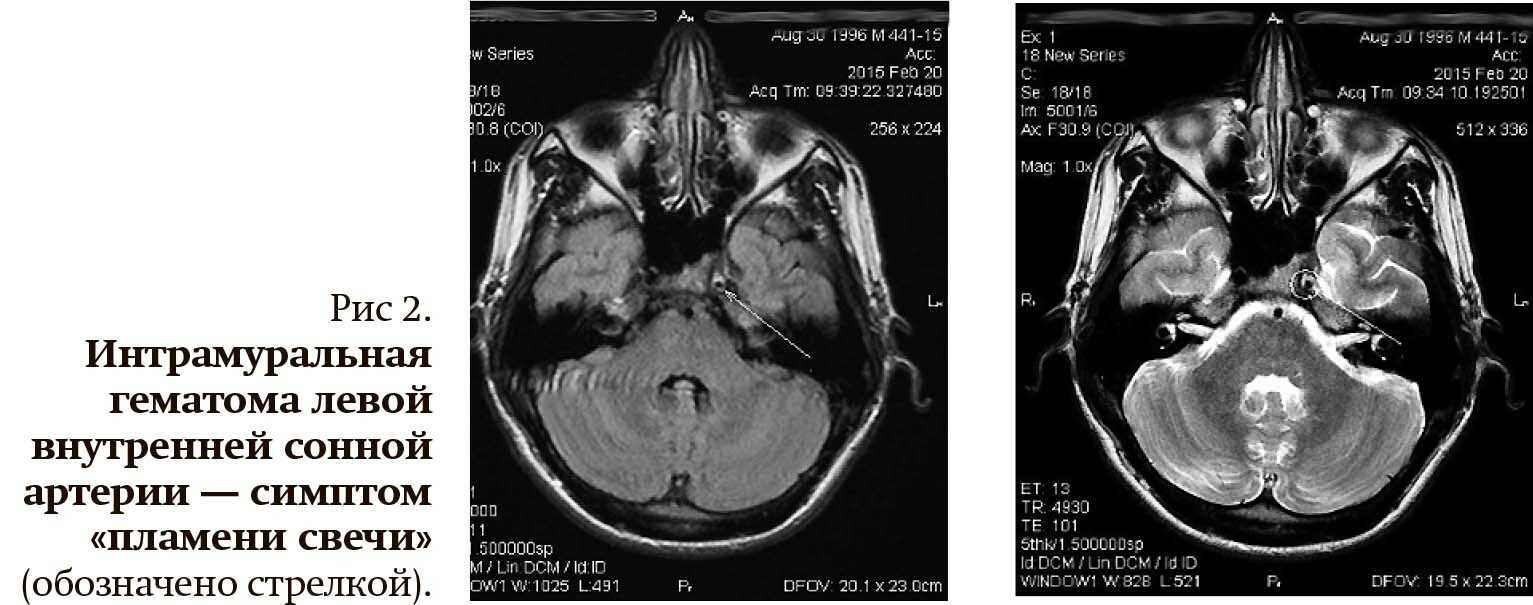

• конусообразное предокклюзионное сужение артерии на 2–3 см выше ее устья — симптом «пламени свечи» (рис. 1, 2);

Магнитно-резонансная томография по сосудистой программе выявляет большинство патогномоничных для диссекции признаков: симптом «пламени свечи», неравномерное сужение артерии (симптом четок), аневризмы, однако чувствительность этой техники в диагностике диссекции ниже, чем КТА. Большое диагностическое значение имеет МРТ с подавлением жира в режиме Т1, которое позволяет выявить наличие интрамуральной гематомы внутри стенки сосуда.